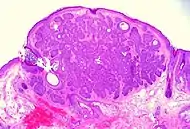

Micrograph of a basal-cell carcinoma, showing the characteristic histomorphologic features (peripheral palisading, myxoid stroma, artefactual clefting). H&E stain

Basal-cell carcinoma is named after the basal cells that populate the lowest layer of the epidermis due to the histological appearance of the cancer cells under the microscope.[14] Nevertheless, not all basal-cell carcinomas actually originate within the basal layer.[14] Basal-cell carcinomas are thought to develop from the folliculo–sebaceous–apocrine germinative cells known as trichoblasts. Trichoblastic carcinoma is a term used to describe a rare and potentially aggressive malignancy that is also thought to arise from trichoblasts and may resemble a benign trichoblastoma (differential diagnosis can be challenging).[15][16][17] It has been suggested that lesions diagnosed as 'trichoblastic carcinoma' may actually themselves be basal-cell carcinoma.[18]

Basal-cell carcinoma cells appear similar to epidermal basal cells, and are usually well differentiated.[23]